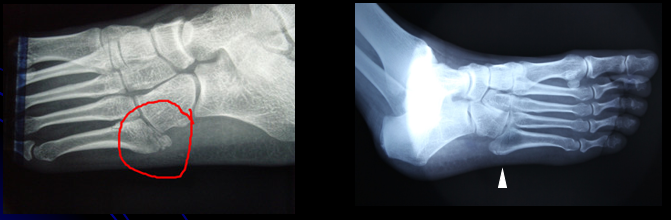

Lawrence 等根据骨折部位把第五跖骨近端骨折分为3区(最常用):

• Ⅰ区:骨折是跖骨粗隆部撕脱骨折,发生率最高;

• 区:骨折是干骺端与骨干连接部骨折,又称Jones骨折,因血运原因容易发生不愈合;

• III区:骨折是跖骨干部的疲劳骨折,多见于运动员

第五跖骨Ⅰ区骨折分型:Ekrol等把第五跖骨Ⅰ区骨折按部位从近而远又分为3个类型:(如图所示)

• 1型:是粗隆尖部骨折;

• 2型:是从第五跖骨基底到第五跖骨-骰骨关节面的斜形骨折;

• 3型:是通到第四跖骨关节面的横行骨折。